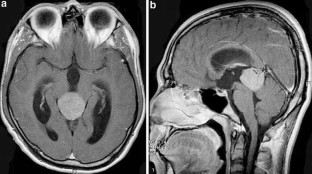

A 21-year-old man who presented with headache and diplopia was admitted to our hospital. Neuroradiological studies revealed a tumor in the pineal region. The tumor was biopsied with endoscope, and third ventriculostomy was performed. Histologically, the tumor proved to be a germinoma. The patient received 3 cycles of combination chemotherapy consisting of carboplatin and etoposide with radiotherapy. The tumor was totally resolute. Twelve months later, he was readmitted with headache and diplopia. Neuroradiological studies showed a tumor in the right temporal lobe.

The second tumor was totally removed. Histologically, the tumor proved to be a mixed germ-cell tumor, which consisted a yolk-sac tumor and a germinoma. After the second course of chemotherapy, magnetic resonance image studies revealed no evidence of the tumor.